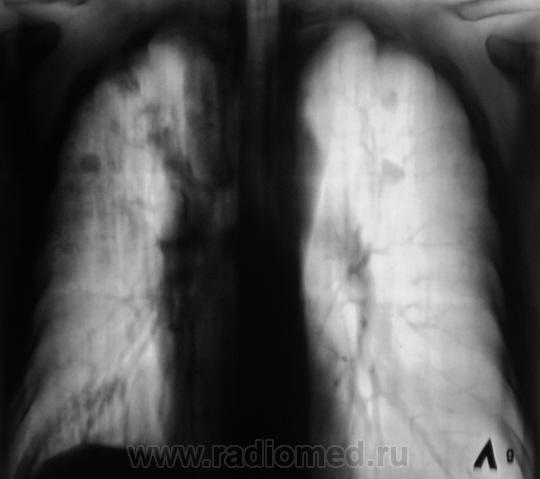

А динамика от проводимого лечения была положительной? А что в шестерке справа, полость? Когда был последний R-контроль?

Последнее "плановое" исследование - 6 мес. тому. Принимает курс "специфической" терапии (таблетированные препараты). Убедительной полости на томограммах не видели.

Если на фоне положительной динамики от лечения идет периодическое подсыпание... Видно,что старые очаговые изменения уплотняются, частично кальцинируются, а тут свежие, однородные... Надо искать источник.

Не возник ли у фтизиатра вопрос о резистентности к принимаемым препаратам? Все-таки картина характерна для тбц.